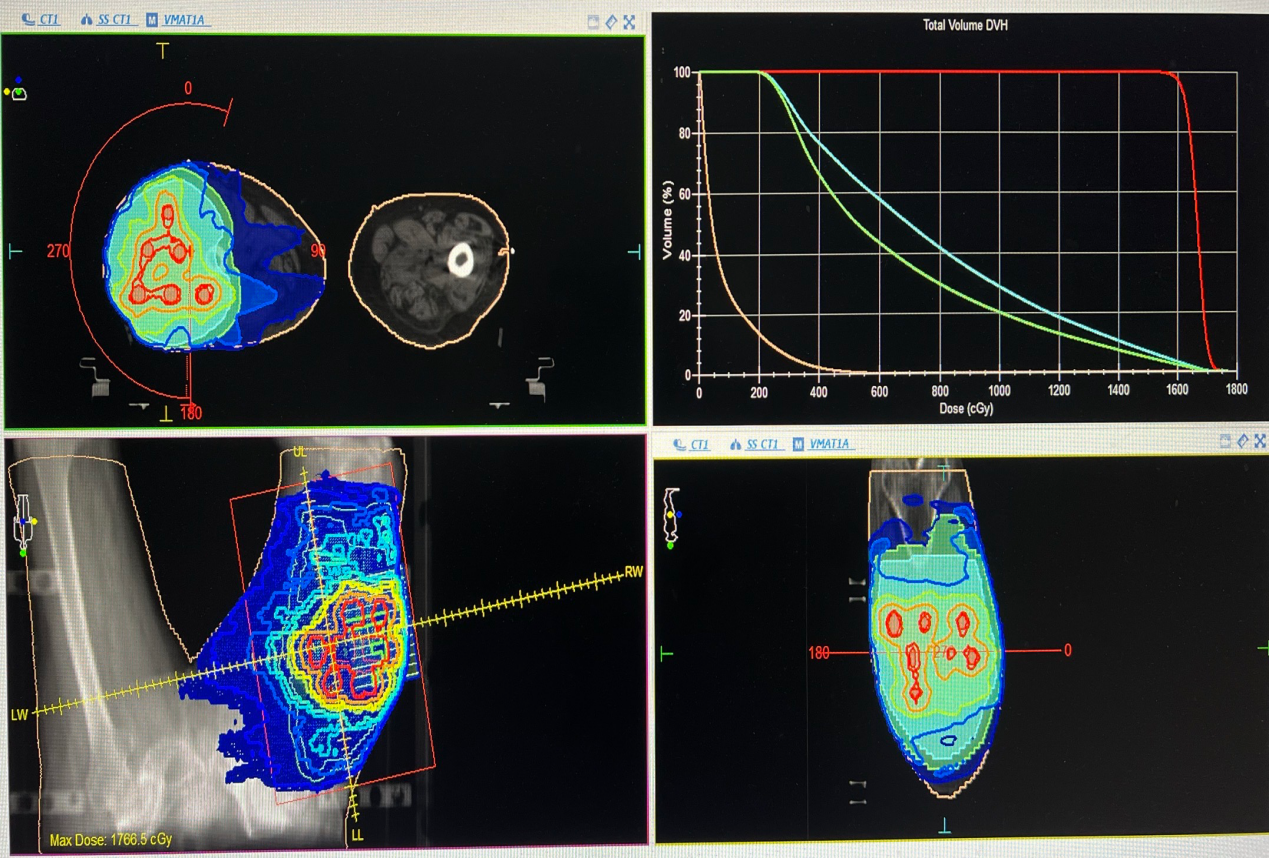

空间分割放射治疗(SFRT)是一种前沿的放疗技术,它巧妙地在肿瘤中心聚焦极小范围的高剂量(峰剂量),而在肿瘤周边则施以相对低剂量(谷剂量)。这种独特的峰谷剂量梯度设计,不仅直接杀灭肿瘤细胞,还能激活免疫系统,从而达到既控制肿瘤又保护正常组织的目的。

图中所示红色为高剂量区(峰),蓝色为低剂量区(谷)。